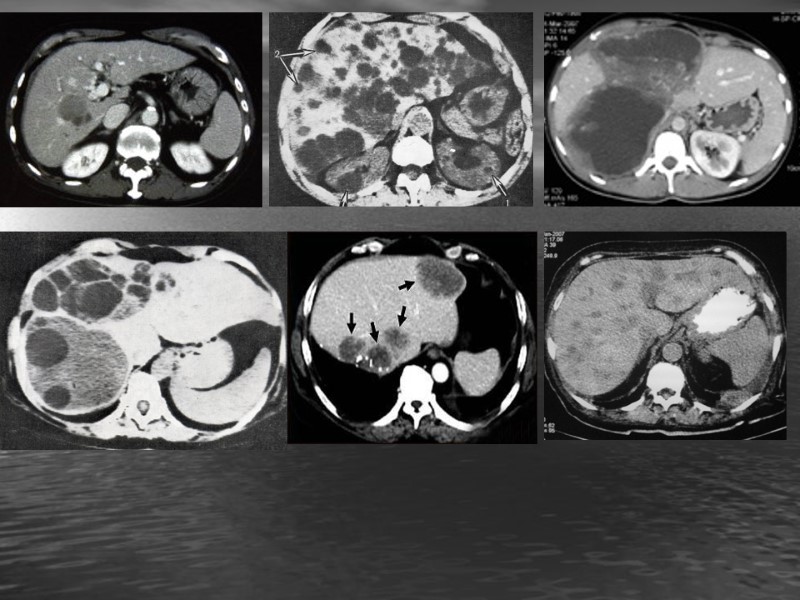

КТ-семиотика Форма, размеры, положение, контуры печени. Локализация участков поражения, их количество, денсивность (изо-, гипо-, гипер-, гетеро-), форма, размеры, контуры, структура, состояние окружающих органов.

КТ- семиотика ВС – гиперденсивный очаг в проекции печени и или ЖП МС – опухоль, камень (рентгенпозитивный конкремент), метастазы, обызвествление

ВС: Гиподенсивный участок в паренхиме или в ЖП МС: опухоль, киста, паразиты (альвеококк, эхинокок), метастазы

Абсцесс печени Круглая или неправильная форма, неоднородная структура, Гиподенсивный очаг(10-20 ед. Н.). После в\в усиления при КТ и МРТ контраст накапливается в области капсулы и около абсцесса.

Цирроз - рак Опухоль небольших размеров нечетко дифференцируется п о с л е контрастного усиления НАТИВНАЯ ФАЗА ОТСРОЧЕННАЯ ФАЗА